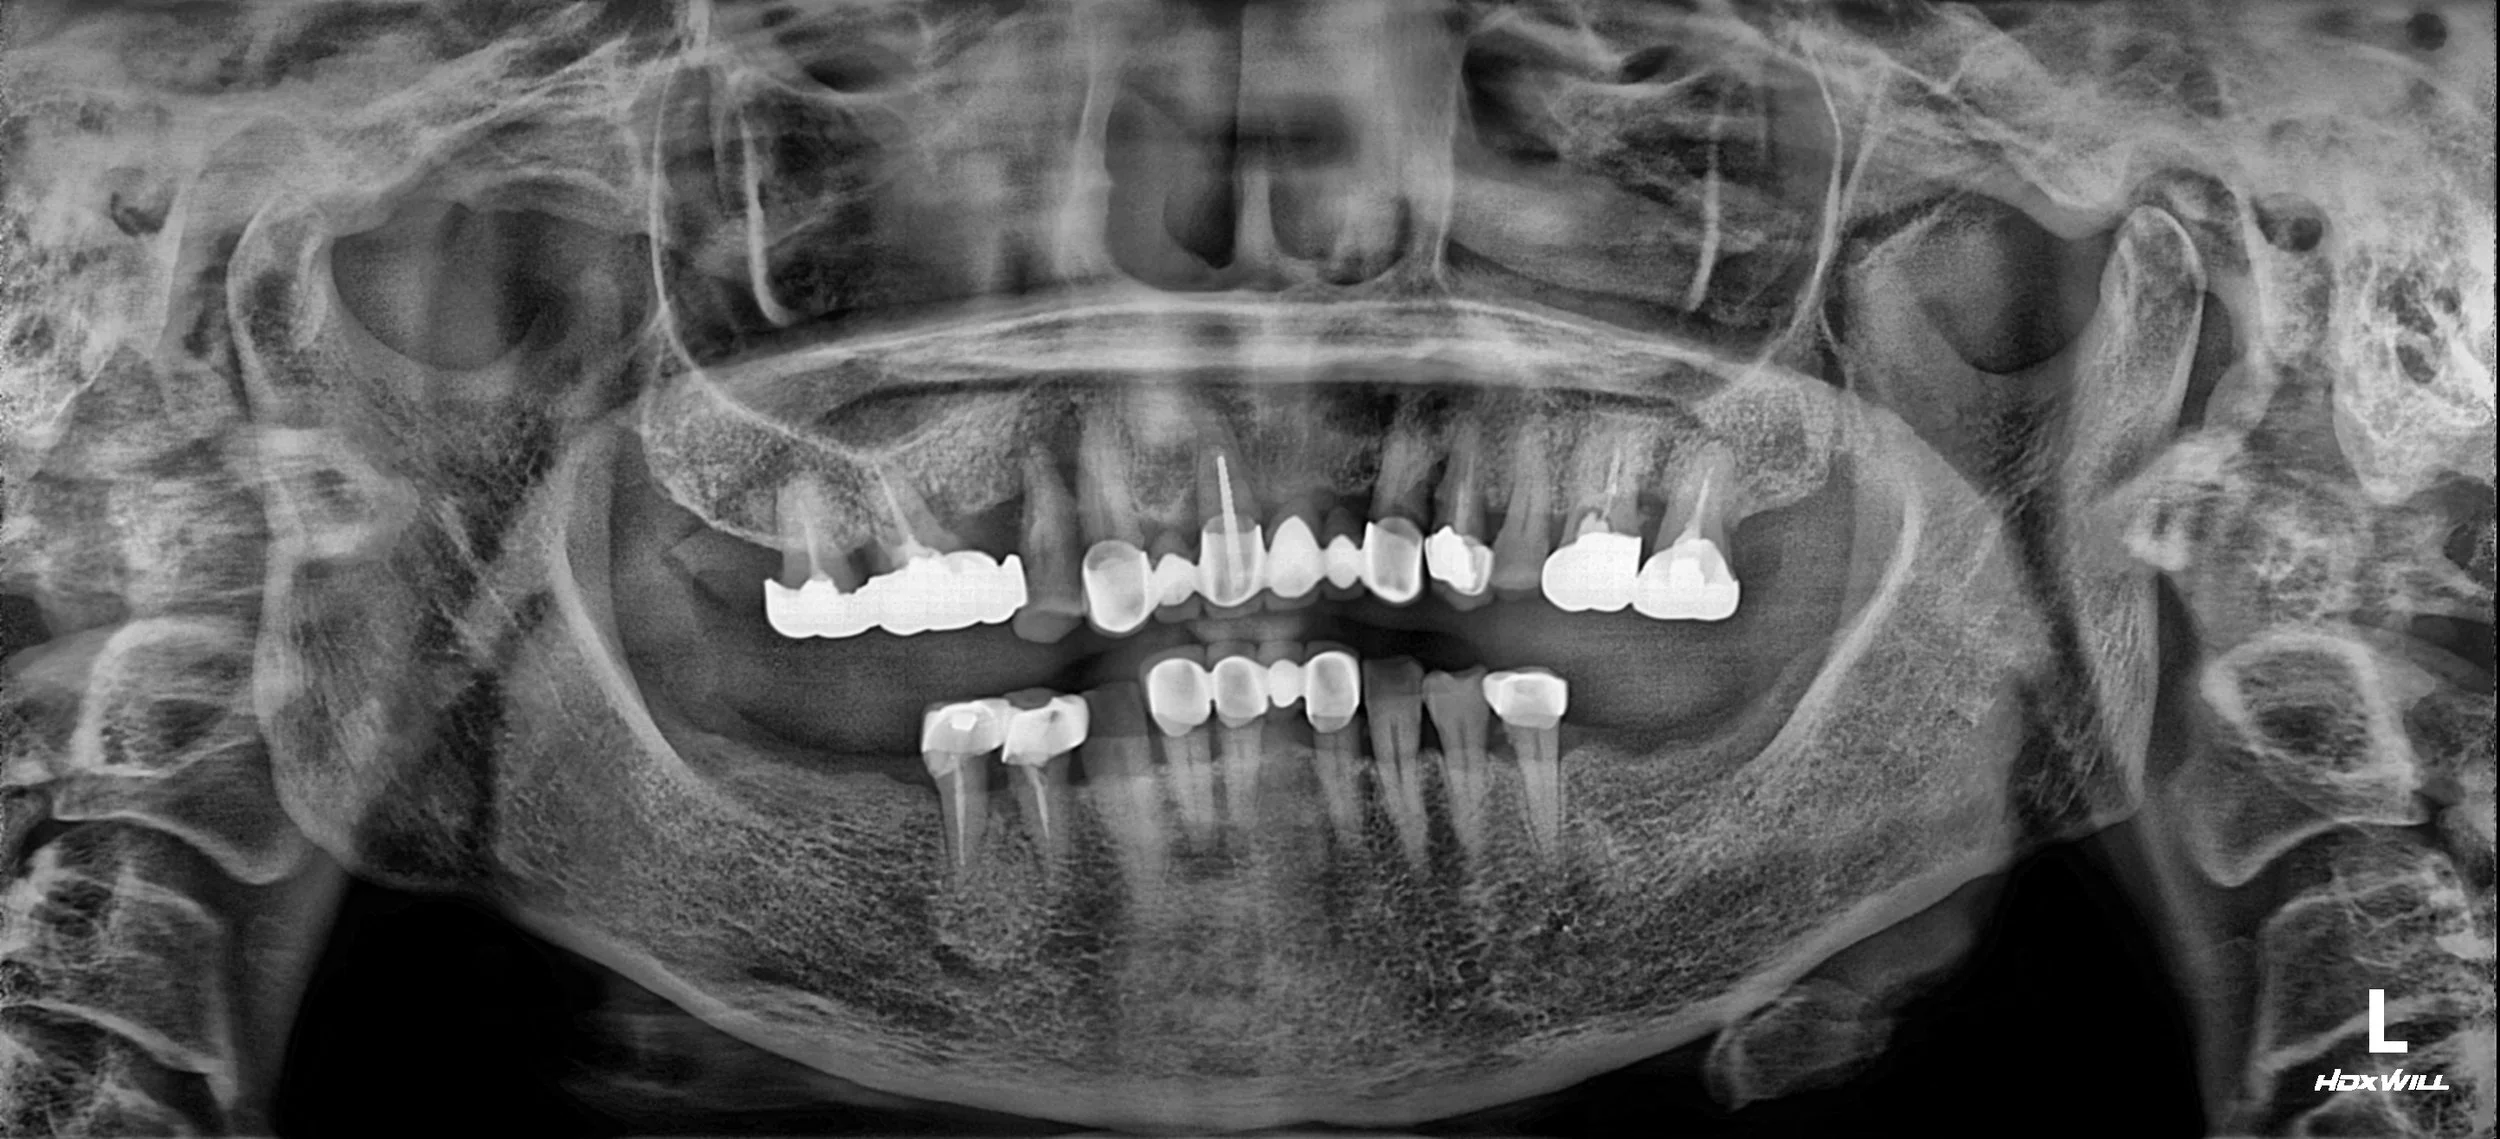

OPG - BEFORE

The patient had worn removable dentures for several decades without proper

restoration of the vertical dimension.

Progressive loss of occlusal height resulted in chronic mandibular retrusion,

temporomandibular joint symptoms, and insufficient prosthetic clearance

for posterior implant rehabilitation.